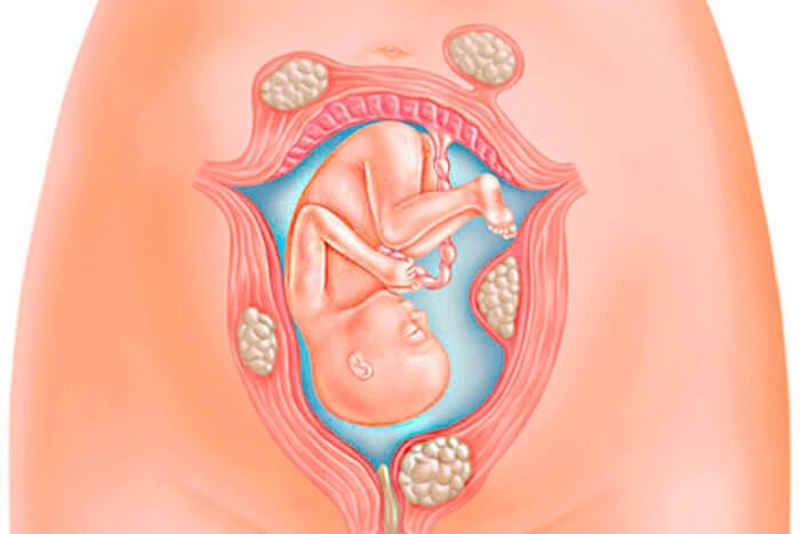

Ước tính từ 40% đến 60% phụ nữ mắc phải các khối u cơ trong tuổi 35. Và con số này nâng lên đến 80% ở tuổi 50.Tuy nhiên việc phát hiện khối u xơ tử cung trong thai kỳ là tương đối khó.

Bởi rất khó để phân biệt sự dày lên của cơ tử cung là do u xơ hay do ảnh hưởng của thai kỳ. Hầu hết phụ nữ được chẩn đoán mắc u xơ đều có thai như bình thường, chỉ có một số trường hợp nhỏ có thể gây ra tình trạng nghiêm trọng đối với các mẹ bầu.

U xơ tử cung phổ biến trong độ tuổi tiền mãn kinh